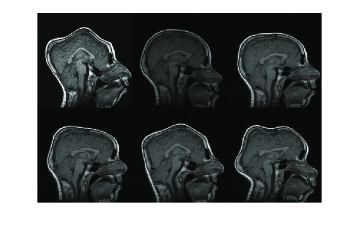

In Figure 9, three example registration results of randomly and nonlinearly warped images are shown. Capturing signal intensity variations during registration process with intensity standardization method leads to assesment of visual comparision of registered source and target images with warping grid. Evaluation of the registration results is summarized in Table-2. The table shows that large and small scale deformations are captured accurately on the standard intensity scale. Resulting images have fixed intensity meanings even there is large intensity variations initially.